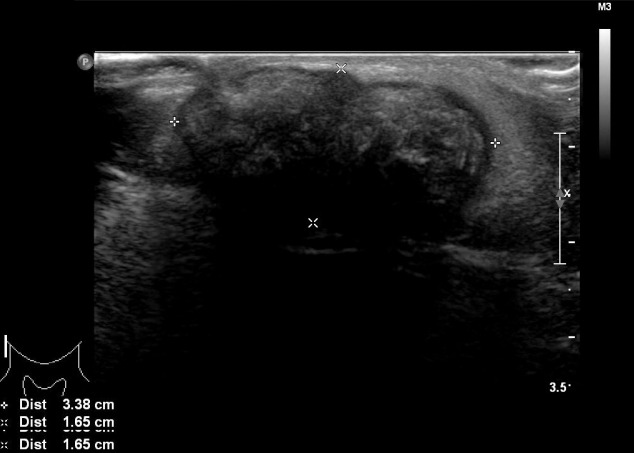

進行超聲檢查以確定腫塊是否為腮腺腫瘤,并顯示與腮腺分離的異質(zhì)腫塊(圖 2)。 進行了頸部對比增強計算機斷層掃描和超聲引導(dǎo)穿刺活檢。 在右下頜角,它表現(xiàn)為邊界清楚、分葉狀和不均勻強化的腫瘤,在皮下脂肪層和淺表肌肉腱膜系統(tǒng)中有鈣化部分(圖 3)。 穿孔活檢顯示與毛母質(zhì)瘤一致的特征,并且在超聲引導(dǎo)下對頸部淋巴結(jié)進行抽吸活檢時未發(fā)現(xiàn)腫瘤細胞。

圖 2:超聲檢查顯示與腮腺分離的異質(zhì)性病變